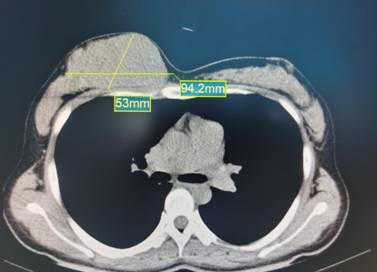

经彩超检查提示,患者右侧乳腺占位性病变,肿瘤几乎占据整个右乳的1/2 ,大小约10.0cmx10.0cm。由于患者乳晕小,肿瘤太大,若通过乳晕美容切口实施手术,难以切除。如采用传统手术方式切除,术后将在患者乳房上留下长而明显的手术瘢痕。患者及家属都表示难以接受。